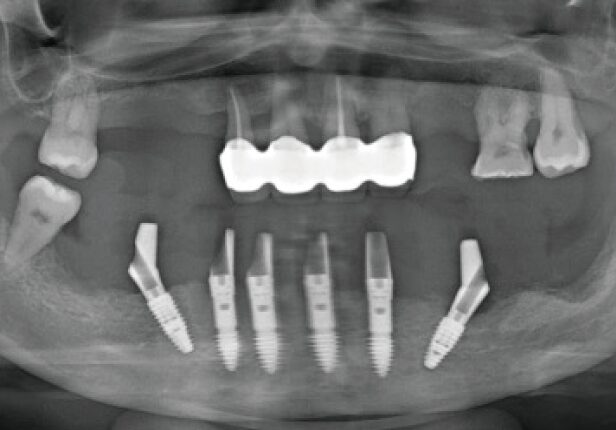

Panorâmica pré-cirúrgica

Panorâmica pós-cirurgia

Panorâmica Final da Coroa

Panorâmica Pós-Cirúrgia